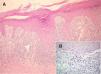

El examen histopatológico mostró un infiltrado inflamatorio de tipo liquenoide, que se extendía a la dermis media (fig. 2A). La composición de este infiltrado era polimorfa con presencia de linfocitos, células plasmáticas, histiocitos y una presencia notable de eosinófilos. La epidermis mostraba una hiperplasia epidérmica irregular, con hipergranulosis e hiperqueratosis compacta sin paraqueratosis. Existía una discreta espongiosis. No se observaba migración transepidérmica de células inflamatorias. Por otro lado, sí destacaba la presencia de hendiduras dermo-epidérmicas, queratinocitos apoptóticos basales e incontinencia pigmentaria (fig. 2B). Se apreciaba un reforzamiento periecrino en la dermis profunda.